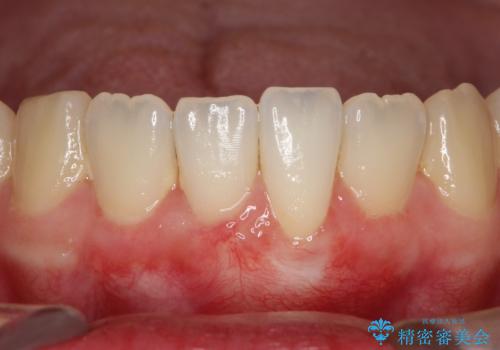

下顎前歯の歯肉退縮 結合組織を用いた根面被覆

- 歯肉退縮を主訴に来院された患者様です。

口蓋から結合組織を採取して、根面被覆を行いました。

十分な根面被覆を達成で患者様にも満足していただけました。